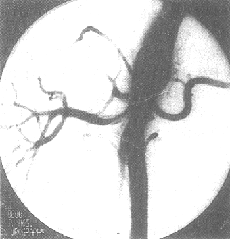

DSA的分辨率足夠觀察腎實質內直徑小至1mm的血管,可診斷腎動脈病變達91.1%,有參考價值者6.6%,只2.3%影像不能作出診斷。DSA可以區分纖維肌肉發育不良、動脈粥樣硬化、腎萎縮、腎動脈細小或腎動脈閉塞等症。在顯影不夠滿意的病例,可因腎動脈開口處極度狹窄致使顯影劑密度不足而影響腎內血管小分支的濃度,也可因動脈的重疊或心排血量不足所致。DSA可測出腎內血液分佈的數值、灌注情況、積蓄功能以及廓清功能等,從而可準確地評估兩腎的生理功能(圖5、6)。

圖5 腹主-腎動脈造影─DSA

圖6 腎動脈造影─DSA